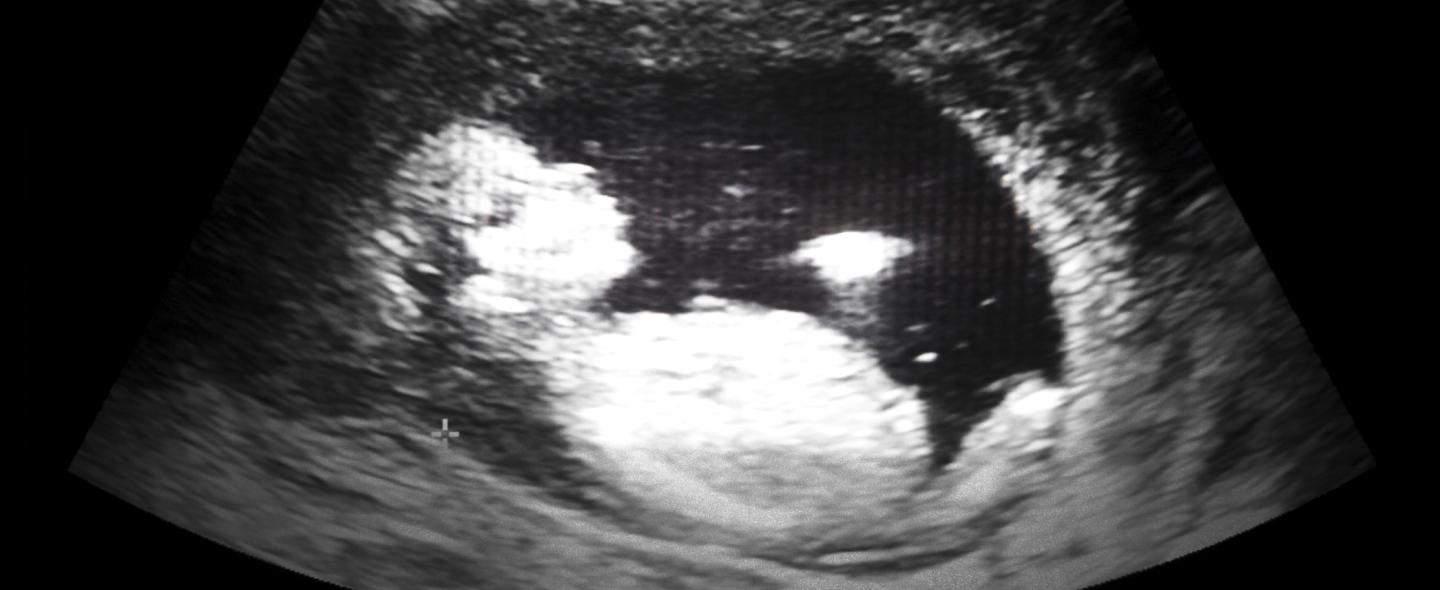

Kasvavan sikiön luusto ja hampaisto tarvitsevat kehittyäkseen kalsiumia sekä D-vitamiinia. Jos äidin ruokavalio ei sisällä riittävästi kalsiumia, suositellaan kalsiumvalmisteen käyttöä. Myös D-vitamiinilisää suositellaan raskausaikana.